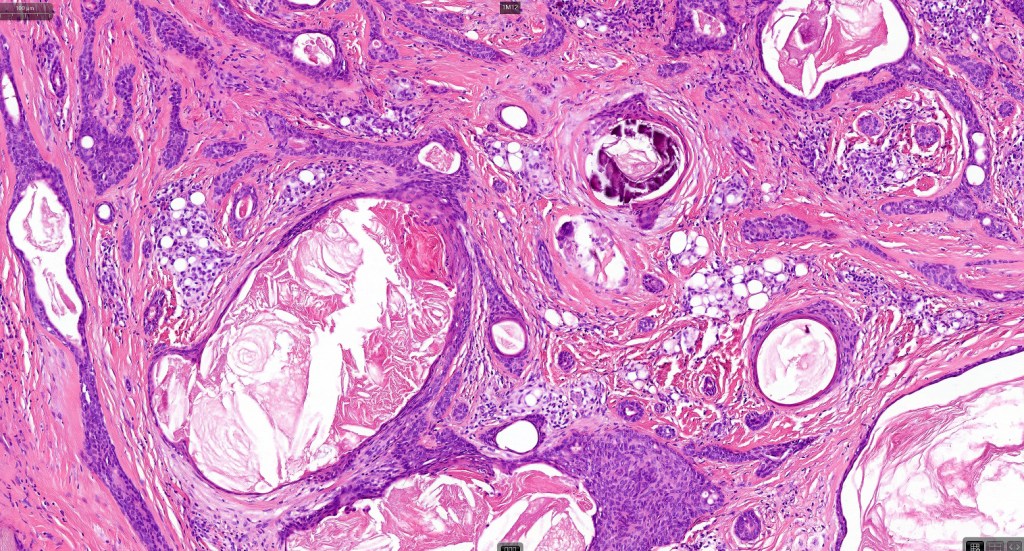

Histological features

•Well circumscribed unencapsulated, nodular/multinodular silhouette composed of an admixture of epithelial & mesenchymal elements

•Often intensely basophilic due to mucinous deposits

•Mucinous metaplasia

•Ductal differentiation

•Cribriform/retiform appearance occasionally evident

•Follicular & sebaceous differentiation

•Keratocysts & squamous foci

•Stromal sclerosis & hyalinization

•Myxoid change

•Chondroid foci

•Calcification & osteoid